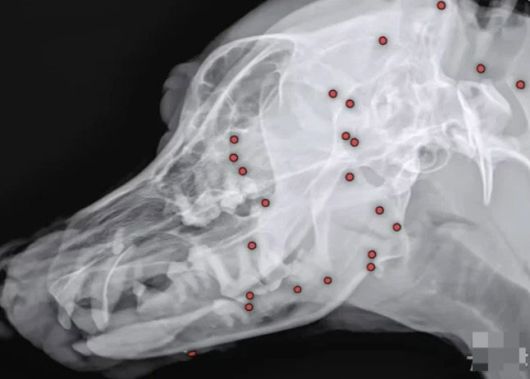

구조 당시 겉으로 보기에 드러나지 않던 산탄총 총알들은 원인을 알 수 없는 이유로 백구 온 몸에 박혀 있었고, 동물병원에선 엑스레이, CT(컴퓨터단층촬영) 등 정밀검사에 들어갔다.

안승엽 VIP동물의료센터 원장은 “총알이 머리 쪽부터 어깨, 가슴통, 엉덩이, 다리까지 너무 많이 있었다”며 “살아있는 게 기적”이라고 밝혔다.

산탄총 파편 제거 수술은 총 3시간 동안 진행됐다. 맨눈으로 탄알을 다 확인할 수 없어서 투시기를 이용해 일일이 수술해야 했다고.

안 원장은 “탄알을 한 번에 다 제거하기는 현실적으로 어려워 백구의 얼굴을 위주로 최대한 많이 제거하는 방향을 선택했다”며 총 26개의 파편을 제거했다고 밝혔다.

수술 후 백구의 얼굴 부분에서만 총알 26개가 제거됐다. 백구의 엑스레이 사진. (사진=VIP동물동물의료센터) |